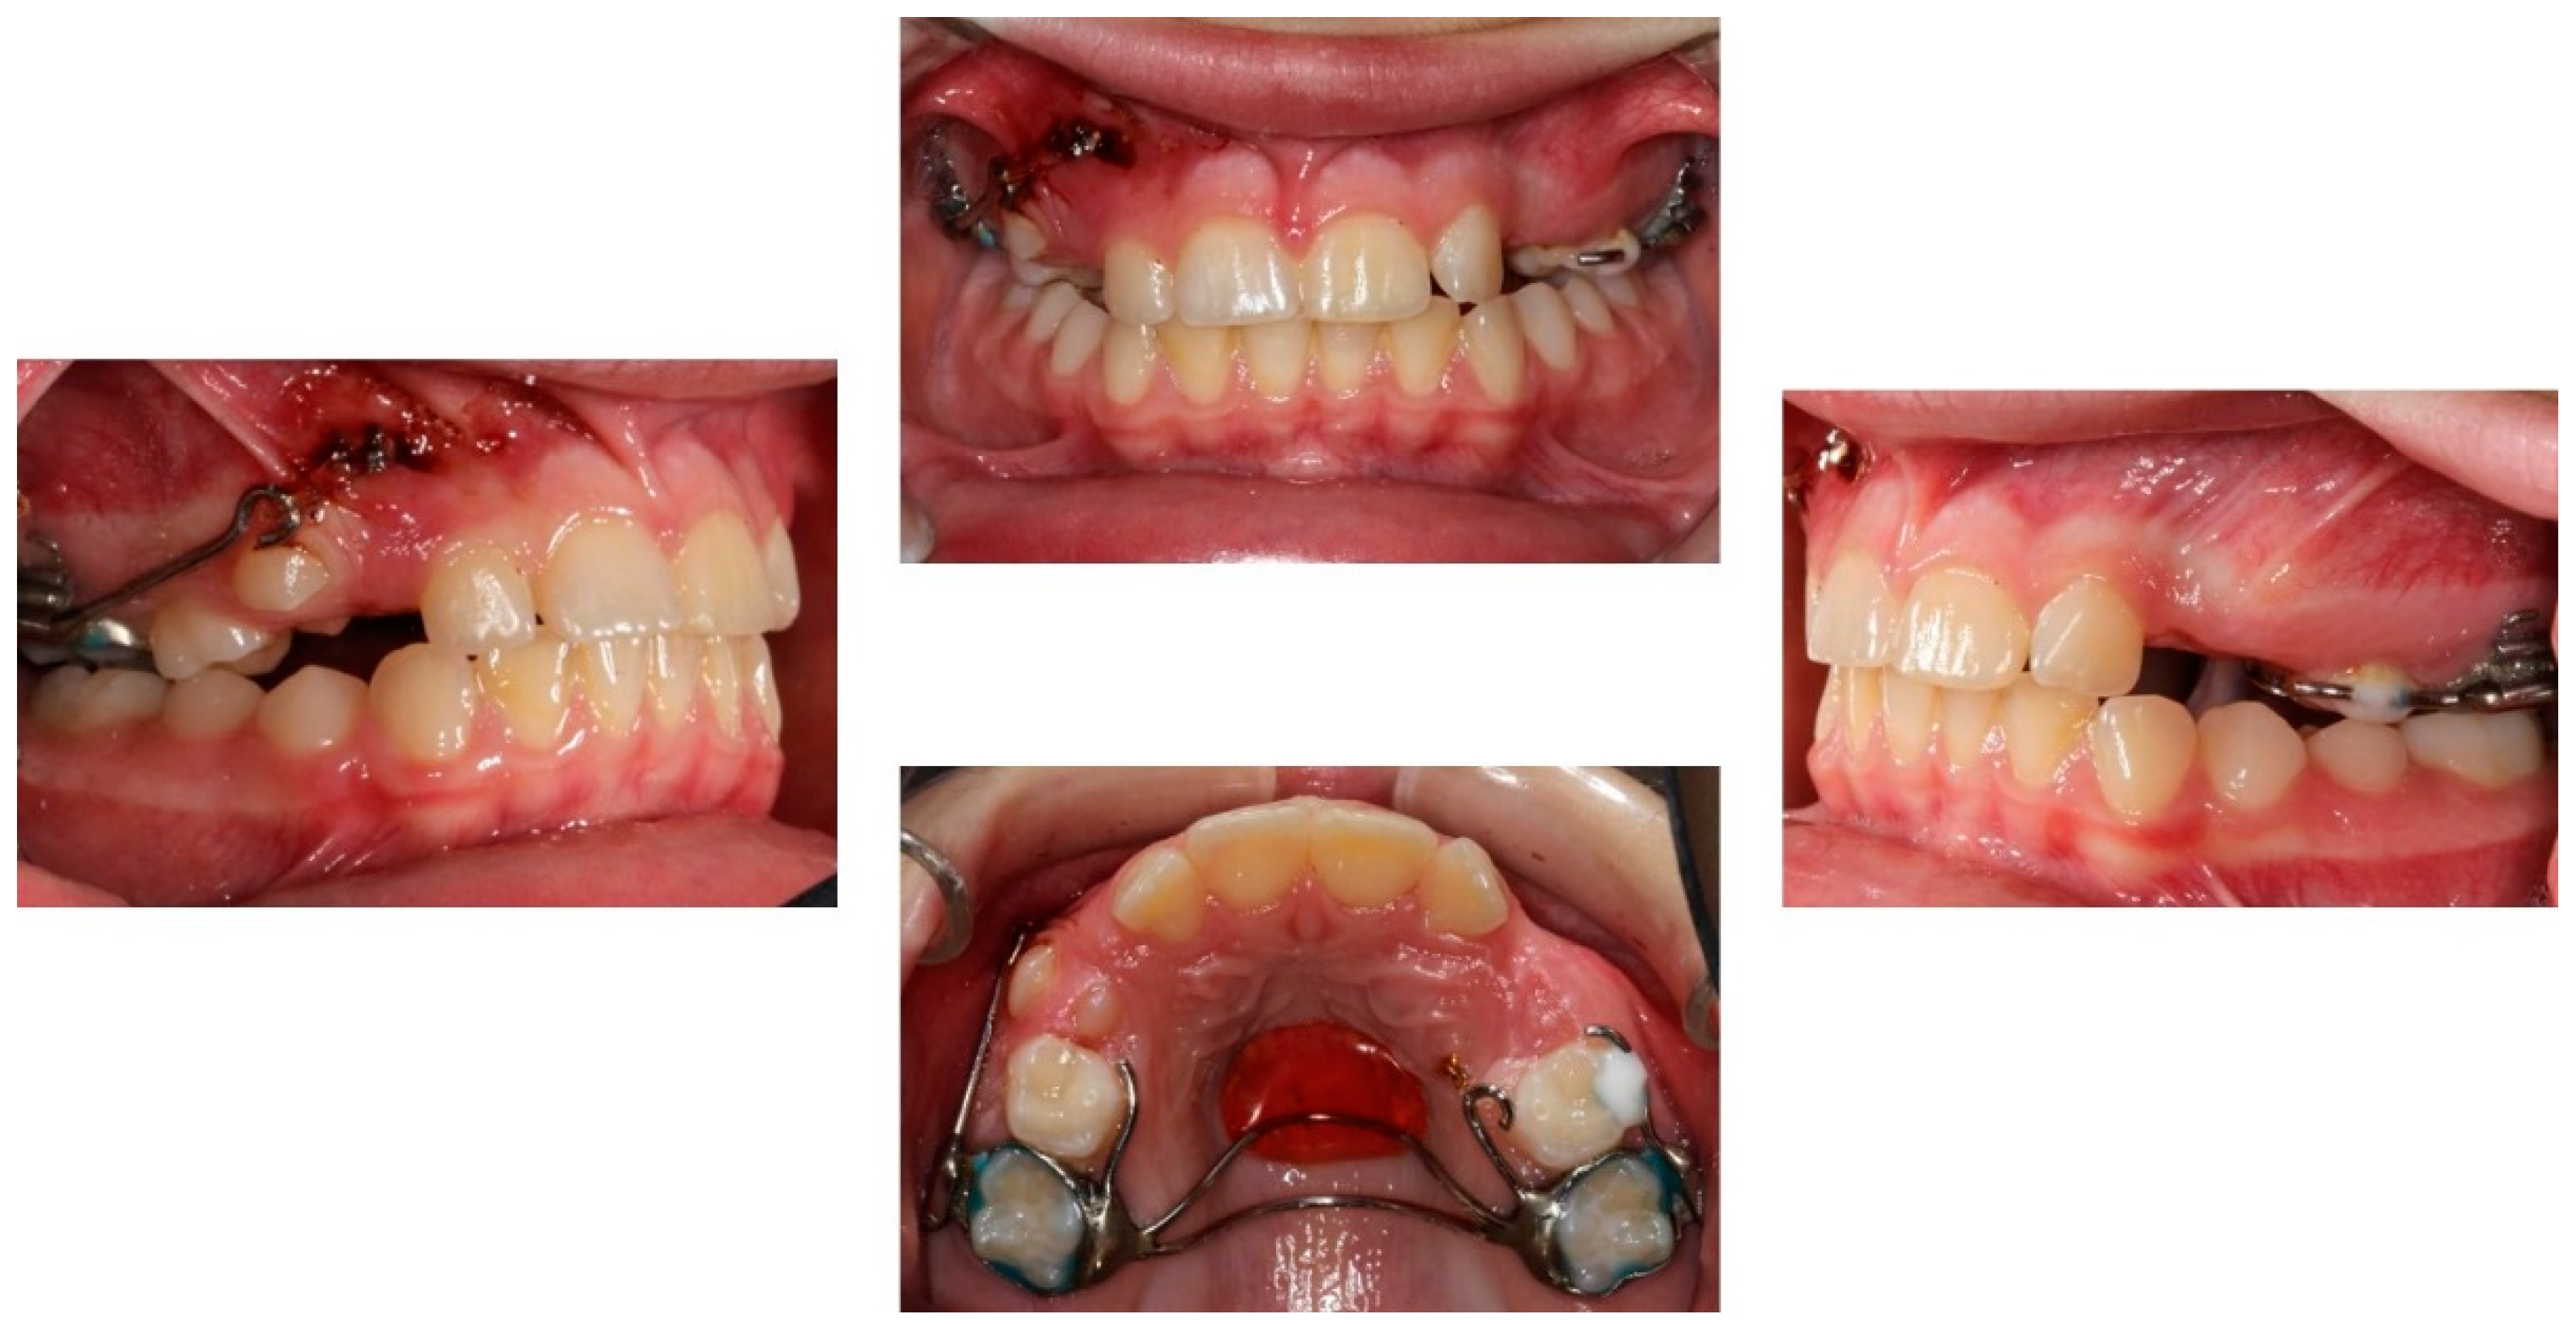

Extra-oral examination of the child revealed a convex profile, slightly reduced lower facial height and increased labionasal angle. Intra-oral clinical examination showed a mixed dentition in Class II molar relationship, reduced overjet (2 mm) and overbite (10%) (Figure 1). Patient’s oral hygiene was good.

Figure 1.

Pre-treatment extra- and intra-oral photographs.

The orthodontic treatment was initiated with the canine exposure (Figure 5) and traction with light forces using a custom-made trans-palatal arch for anchorage purposes (Figure 6 and Figure 7). An open surgical technique (apically positioned flap) was used to expose the labially positioned right canine and a closed technique for the left, which was positioned palatally. Sectional mechanics were applied during treatment until the eruption of all permanent teeth (Figure 8). The upper lateral incisors were extracted after the successful eruption of the impacted canines and for aesthetic reasons. Subsequently, comprehensive orthodontic treatment was performed using fixed 0.018-inch-slot edgewise appliances. A lower lingual arch was placed to preserve the leeway space thus helping with the lower crowing. The progression of the archwire sequence was from 0.014-inch nickel-titanium to 0.016-inch Australian archwires. Class III light elastic forces were used bilaterally to help with space closure on the upper arch.

Progress photographs of the custom-made trans-palatal arch used for the traction of the impacted canines.

Figure 8.

Sectional mechanics used for the traction of the impacted canines.